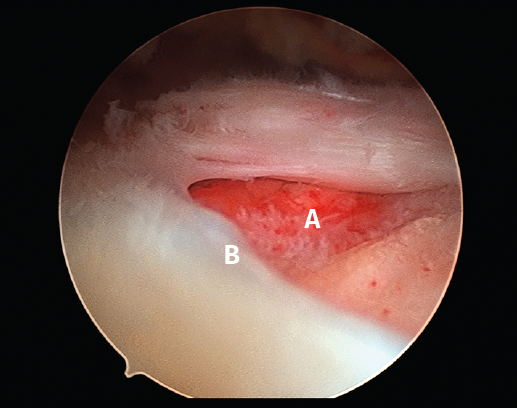

Figura 3. Rotura del manguito rotador en forma de L. A: tendón infraespinoso; B: tendón supraespinoso; C: glena; D: cabeza humeral.

Sin embargo, las clasificaciones basadas en el tamaño de la rotura deben ser bidimensionales, ya que la visión unidimensional puede ser engañosa, al mostrar el tamaño de la rotura solo desde el plano anteroposterior(4). Por esta razón, proponemos el sistema de clasificación del manguito posterosuperior sugerida por Snyder, que aporta información no solo del tamaño, sino del número de tendones afectados y la presencia de tejido cicatricial(7). En las lesiones de tipo C1 la lesión atraviesa todo el espesor del tendón y en el eje transversal es pequeña y punzante (Figura 5). Las de tipo C2 son roturas de espesor completo pero la distancia entre los extremos de la rotura es menor de 2 cm con escasa retracción (Figura 6). En las de tipo C3 la rotura afecta en sentido transversal entre 3 y 4 cm con mayor retracción implicando 2 tendones (Figura 7). Y las de tipo C4 son la rotura masiva del manguito de los rotadores con una afectación de espesor completo de toda la anchura de 2 o más tendones asociando importante retracción (Figura 8).

Figura 10. Grado 2 de la clasificación de Patte. A: rotura retraída del tendón supraespinoso; B: glena; C: cabeza humeral.

La clasificación más utilizada para describir la retracción tendinosa es la realizada por Patte, que utiliza la distancia entre el tendón retraído y su inserción original en el troquiter en el plano coronal. El grado 1 describe una rotura con retracción mínima, en el grado 2 el tendón está retraído medial a la huella de inserción, pero no llega a la glena, y el grado 3 representa una rotura retraída a nivel de la glena (Figura 10). Tanto los estudios de imagen como la evaluación intraoperatoria permiten definir una buena estrategia quirúrgica para realizar una buena liberación de las partes blandas y predecir el pronóstico de la reparación(18,19).